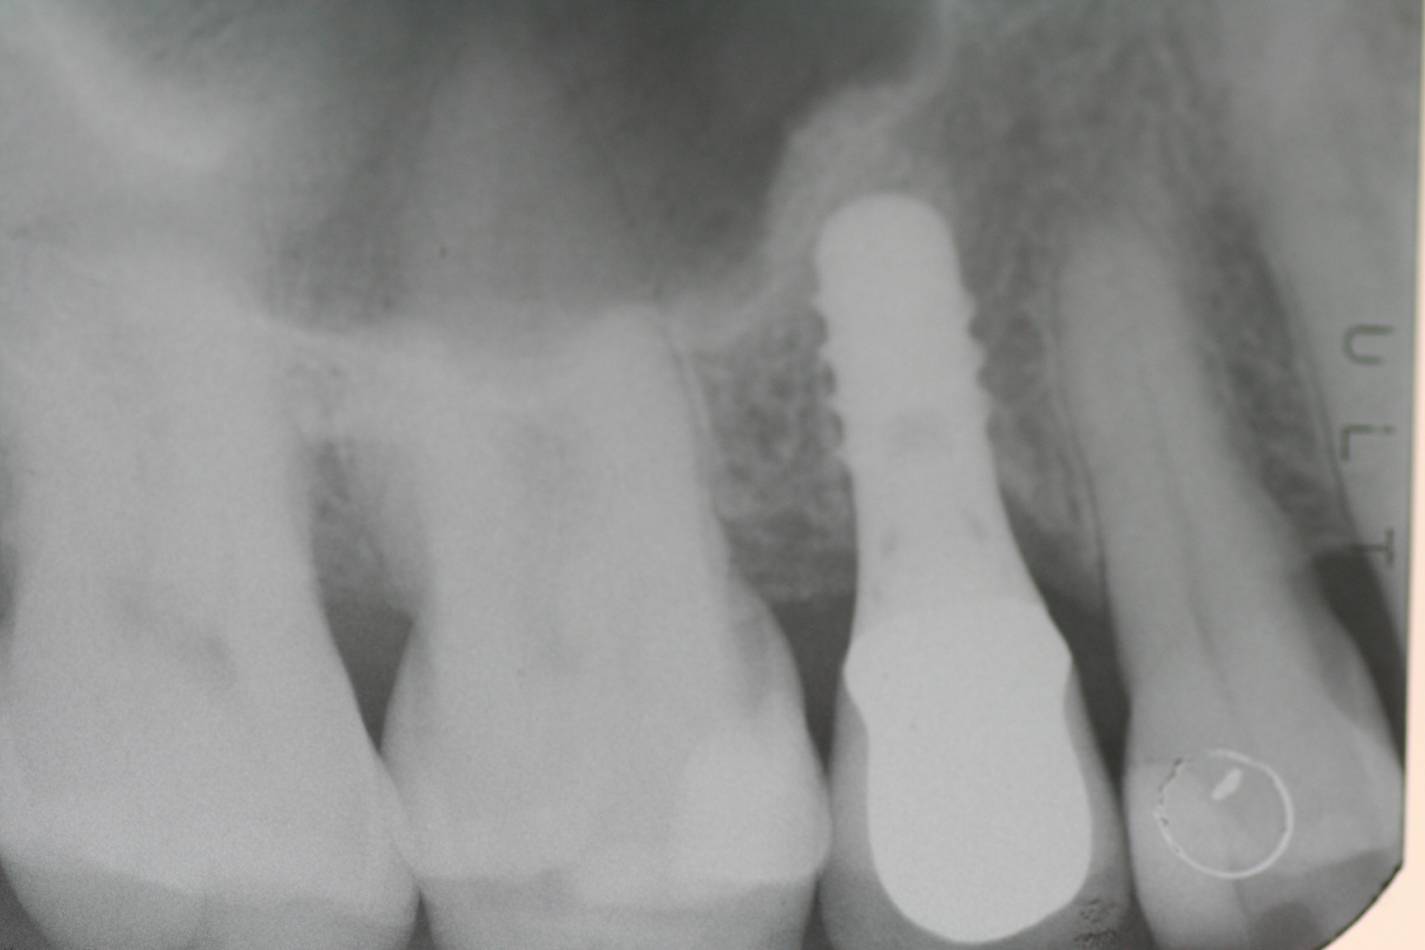

Si effettua implantologia con impianti STRAUMANN e tecnologia IDI EVOLUTION.